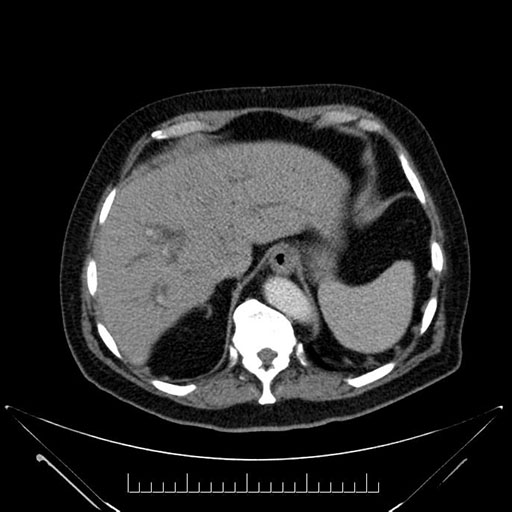

Whipple (pancreaticoduodenectomy) [case 7]

Imaging Analysis

Look through the patient's CT scan to identify any areas of concern for the necessary procedure.

Based on your CT findings, which issue(s) would give reason for "planned slowing down moment(s)" in this case?

Considering a standard Whipple procedure, what step(s) of the operation would you do differently in this case?